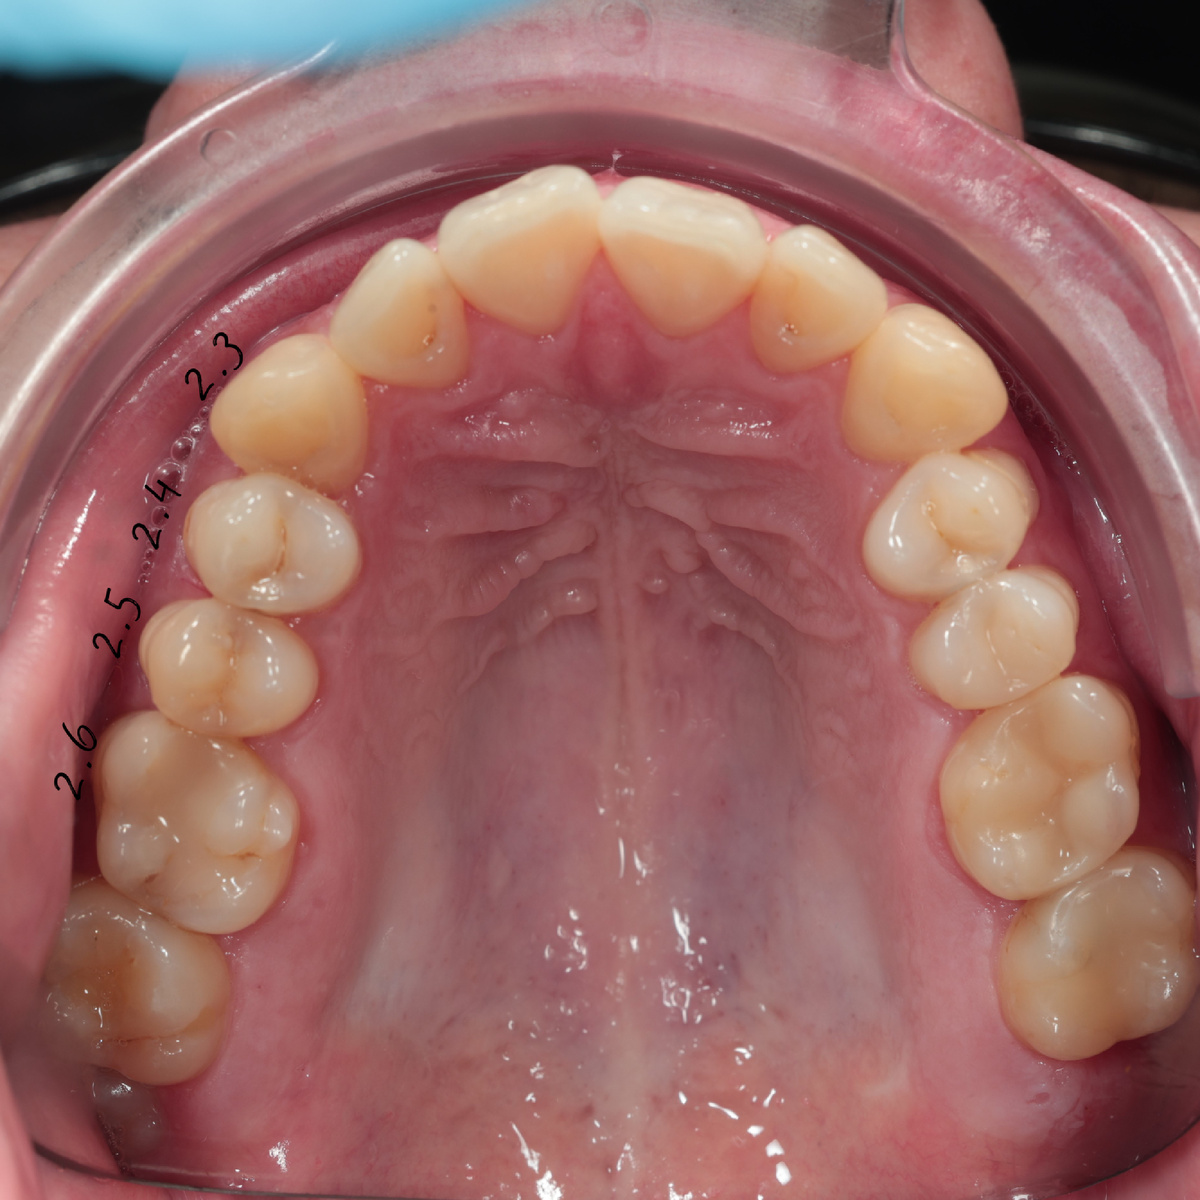

Когда пациент наконец пришел ко мне, конечно сделали снимок, потому что изначально пациент подозревал о кариесе под пломбой на зубе 2.6, который был лечен более 5 лет назад, но я сразу поняла, что дело не в нем.

Снаружи все выглядело вполне прилично, а между зубам-уже строилась настоящая кариозная «недостройка»

Так и не угадаешь, где поселился кариес ?!

Ну что, какой будем лечить? На вид все симпатяги